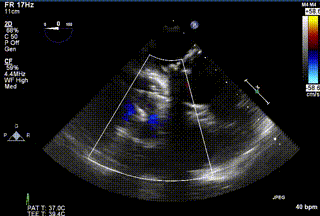

2021年12月24日,復(fù)旦大學(xué)附屬中山醫(yī)院葛均波院士團(tuán)隊(duì)成功應(yīng)用LuX-Valve Plus為一例極重度三尖瓣反流(TR)合并房顫、房缺的患者完成了經(jīng)血管三尖瓣置換術(shù),這是在前基礎(chǔ)上,本周完成的第三例經(jīng)血管三尖瓣置換手術(shù),葛均波院士、周達(dá)新教授等與心外科魏來教授、賴顥教授,心超室的潘翠珍教授、李偉教授及麻醉科的郭克芳教授共同完成了本周手術(shù),均獲得圓滿成功!患者術(shù)后超聲顯示無TR,臨床癥狀明顯改善。本周手術(shù)的成功也為L(zhǎng)uX-Valve Plus救治性臨床研究添上了濃墨重彩的一筆。

三例患者入院后,葛均波院士團(tuán)隊(duì)周達(dá)新教授、潘文志教授、張?jiān)床┦俊㈥惿┦考靶某业呐舜湔浣淌?、李偉教?/strong>對(duì)患者的情況進(jìn)行詳細(xì)評(píng)估和討論,最終決定為三例患者選擇LuX-Valve Plus40mm、50mm和50mm型號(hào)的瓣膜進(jìn)行手術(shù)治療。手術(shù)后即刻拔除氣管插管,術(shù)后患者三尖瓣反流癥狀得到顯著改善,復(fù)查心超結(jié)果顯示人工三尖瓣瓣膜支架固定穩(wěn)定,瓣葉關(guān)閉形態(tài)未見異常,未見明顯反流。